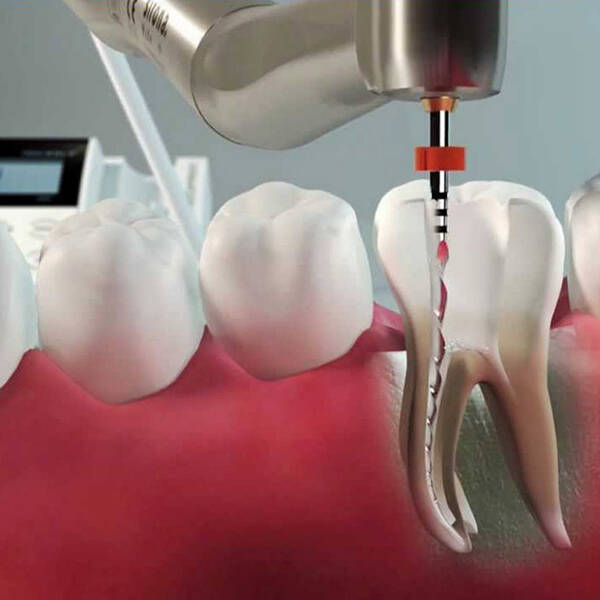

A Endodontia foca no tratamento da polpa dentária (o nervo do dente), que pode ser acometida por infecções, inflamações ou até necrose. Quando o tecido da polpa está comprometido, o tratamento de canal é necessário para salvar o dente e evitar complicações maiores. O procedimento consiste em remover o tecido danificado, limpar e desinfetar o canal radicular e, por fim, preencher o espaço com materiais biocompatíveis que garantem a recuperação e funcionalidade do dente.

- Remoção da Polpa: Quando o nervo está danificado (inflamado, infectado ou morto), ele é removido do interior do dente.

- Limpeza e Desinfecção: O canal radicular é cuidadosamente limpo e desinfetado para remover qualquer resquício de tecido infectado.

- Preenchimento do Canal: Após a limpeza, o canal é preenchido com um material específico que evita novas infecções.